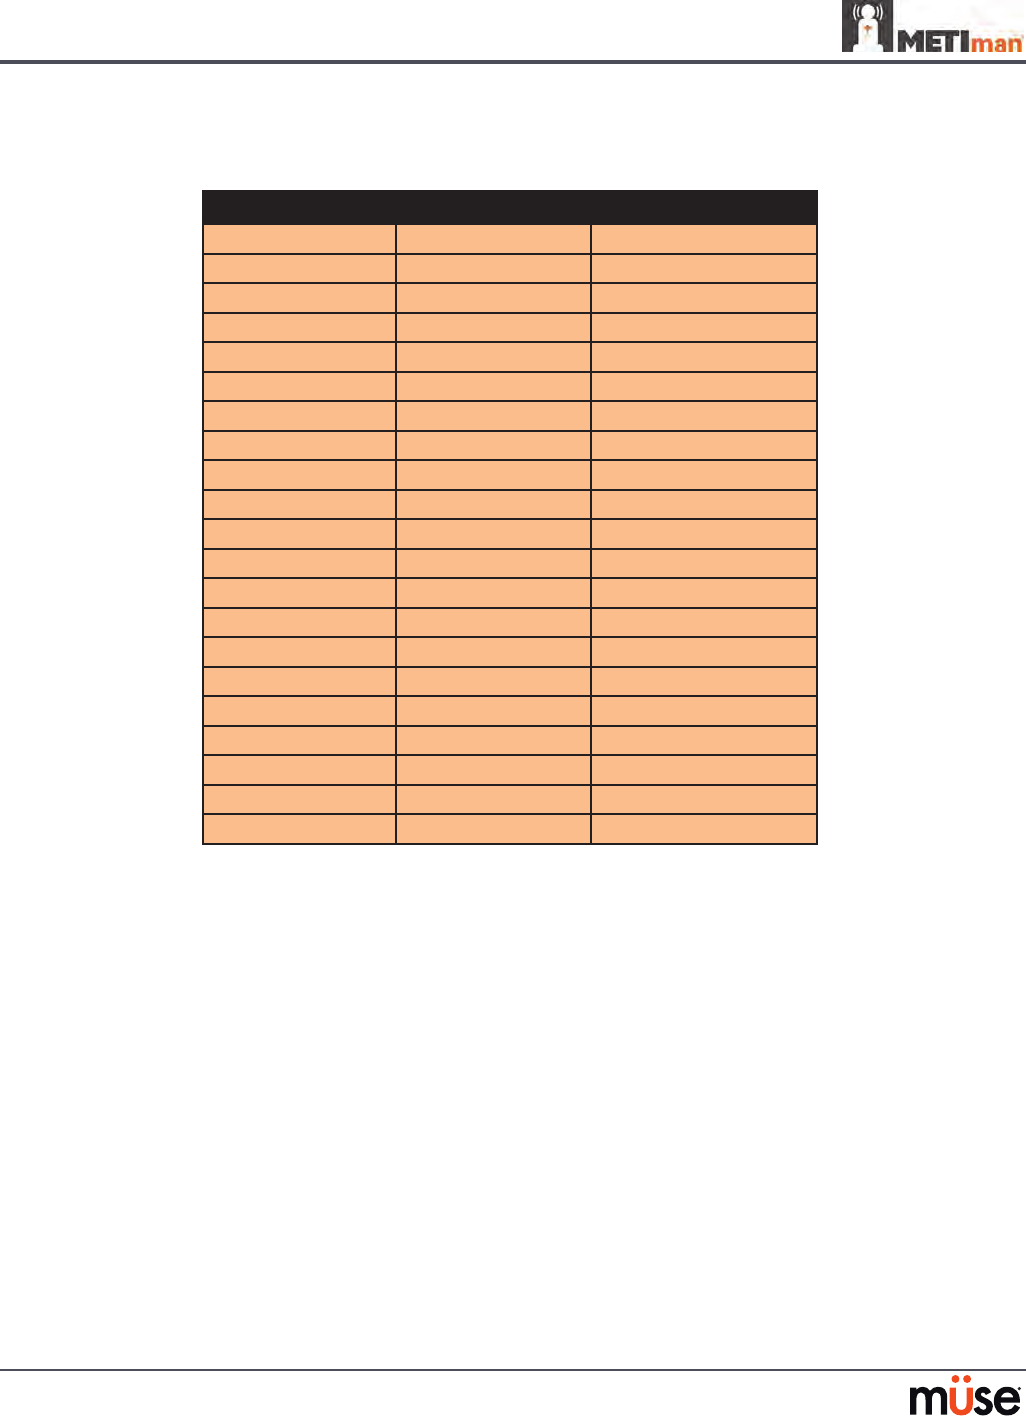

Pulmonary System

Anatomy,

Physiology and

Clinical Signs

Clinical Interventions, Patient Monitoring

and Scenarios.

Software Control

Manual Control

Spontaneous

Breathing

Normal tidal breathing and pathophysiological

conditions such as atelectasis, pneumothorax,

asthma and COPD.

None required, but

adjustable

VIEW: Respiratory

None required.

Exhaled CO2

(Prehospital only)

Measure the presence or absence of CO2 during

positive pressure ventilation.

None required. CO2 canister is

inserted

Pneumothorax or

Hemothorax

Increase in intrapleural volume, leading to

asymmetrical breathing.

None required, but

adjustable

VIEW: Respiratory

CONTROL: Intrapleural

Volume

(Left or Right)

None required.

Chest Excursion Synchronized with ventilation (spontaneous or

positive pressure ventilation). Excursion depth

proportional to tidal volume.

None required. None required.

Breath Sounds Normal and abnormal breath sounds are

independently synchronized with ventilation of

the right and left lungs. Breath sounds can be

auscultated over anterior and posterior anatomic

locations.

None required, but

adjustable

VIEW: Sounds

None required.

Bronchial

Occlusion

Completely obstructs right and/or left mainstem

bronchi, simulating a lower airway obstruction

(e.g. mucus plug). This yields an inability to

ventilate the lungs and asymmetric chest

excursion.

VIEW: Respiratory None required.

Pulse Oximetry Oxyhemoglobin saturation (SpO2) automatically

correlates with the oxygen concentration in the

lungs and the intrapulmonary shunt fraction.

None required, but

adjustable

SpO2 probe is

attached.

Arterial Blood

Gases

PaO2, PaCO2 and pH are continuously calculated,

and the Patient Status Display can be congured

to show them.

None required, but

adjustable

None required.

Venous Blood

Gases

PvO2 and PvCO2 are continuously calculated, and

the Patient Status Display can be congured to

show them.

None required, but

adjustable

None required.

139

Using METIman

Pulmonary System

Needle

Decompression

(Prehospital Only)

Decompression of a pneumothorax can be

performed bilaterally by inserting a needle at the

midclavicular line of the second intercostal space.

The instructor must

adjust the amount

of physiologic

intrapleural air present.

VIEW: Respiratory

CONTROL: Needle

Decompression,

Intrapleural Vol: Left,

Intrapleural Vol: Right

See Needle

Decompression

setup,.